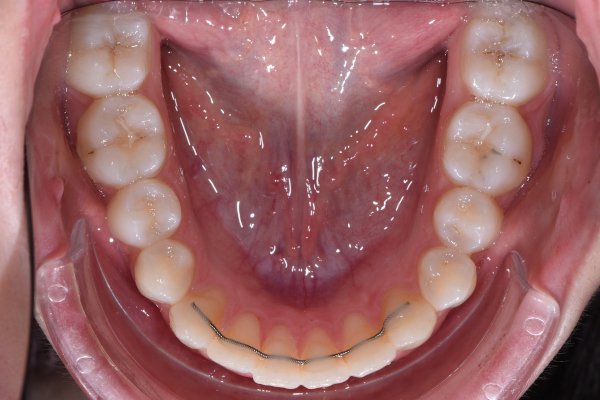

Bonded wire

The wire is glued to the back of your front teeth. The floss is a long-term retention that is meant to stay in place indefinitely. It is therefore important to brush and clean carefully around the wire. If it becomes completely or partially loose, you should contact us as soon as possible. Otherwise, there is a risk that individual teeth may move and a new treatment cannot be offered free of charge.

If you have problems with a splint or wire, you should contact us as soon as possible.